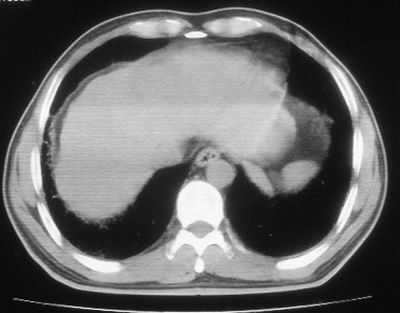

患者,男,44岁,糖尿病4年余,近期消瘦、乏力。化验检查:总胆红素26.33(参考值:5.1-17.2u mol/l),直接胆红素:6.4(参考值:0-4.3u mol/l),谷-丙转氨酶(alt):843(参考值:<40u/l),hbsag(+),抗hbs(-),hbeag(-),抗-hbe(+),抗-hbc(+)。

2\\少量腹水

考虑肺结核,少量腹水.

1.双肺急性粟粒型肺结核;2.少量腹水.